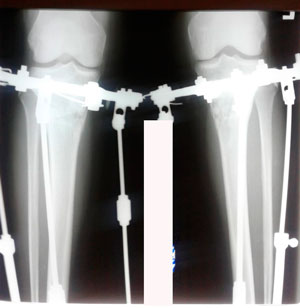

перед крутками

image-28-03-20-10-49-1.jpg